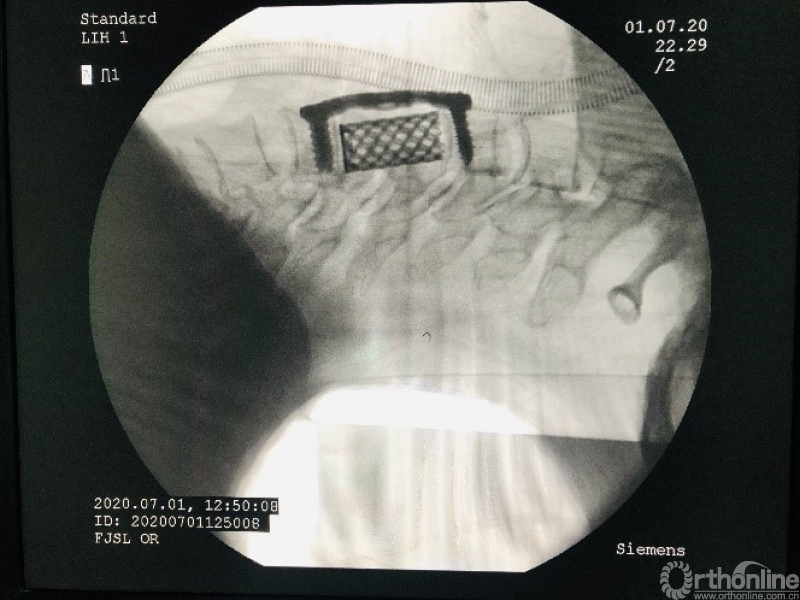

手术方案分析:存在脊髓压迫,为生长于脊髓腹侧硬膜发生的脊膜瘤,有硬膜基底。常规后路手术需要绕过脊髓切除位置固定的肿瘤,入路十分不合理。决定使用ACCF入路,切除硬膜下脊膜瘤。

术后分析:该例颈椎脊髓腹侧脊膜瘤,采用颈前路颈5椎体次全切除入路,避免了后路手术需要牵开脊髓与有重要功能神经根丝的危险操作,是比较合理的一种入路。